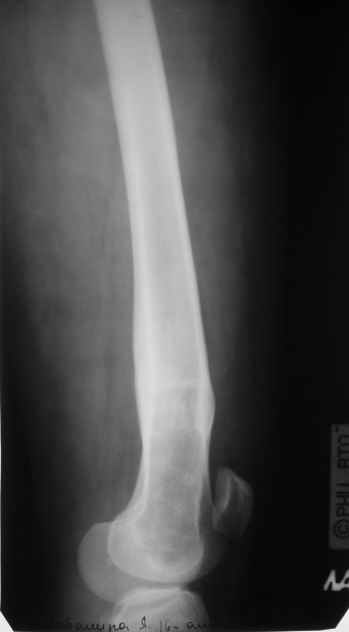

Пациентка 23 лет, доставлена в клинику с Диагнозом: Закрытый сегментарный оскольчатый перелом левой бедренной кости в верхней и средней трети. Травма в результате ДТП 10.03.2006г. Из анамнеза у пациентки диспластический левосторонний коксартроз, S-образный сколиоз 2ст. В 1999г в Кургане выполнялась остеотомия бедра в нижней трети и коррекция укорочения конечности на 3 см (рентгенограммы бедра и таза до травмы в приложении). До получения травмы пациентка ходила без боли с полной нагрузкой на левую ногу. Учитывая дисплазию левого ТБС, пациентке, вероятно, предстоит операция тотального эндопротезирования лев ТБС, что требует анатомичного восстановления проксимальногоотдела бедра. Рассматриваются следующие вариант остеосинтеза:1) Экстракортикальный остеосинтез проксимального и дистального перелома пластиной с угловой стабильностью типа LISS( г Рыбинск); 2) Ретроградный интрамедуллярный блокированный остеосинтез дистального перелома и накостный синтез проксимального пластиной с угловойстабильностью; 3) Остеосинтез бедра в аппарате внешней фиксации с фиксацией таза и возможной открытой адаптацией фрагментов. Хотелось бы узнать Ваше мнение. С уважением Украинский Евгений, г.Краснодар, ККБ N1, ТОО N3.

Судя по снимкам до перелома, большой вертел располагался высоковато. Может, подумать о том, чтобы при остеосинтезе его переместить дистальнее и/или латеральнее? Что скажут коллеги, активно занимающиеся эндопротезированием?

Не во всех случаях, особенно у молодых!, при дисплазии ТБС требуется эндопротезирование. По представленным снимкам четко видны хорошо сохраненный тазобедренный сустав и тем более больная до травмы не имела симптомов диспластического сустава. В будущем при появлении симптомов, можно попытаться сделать реконструктивную работу по сохранению сустава: ПАО с удлинением шейки (аналогичные случаи были

Учитывая, что в проксимальная часть бедра в скором будущем будет нуждаться в больших оперативных вмешательствах, я бы старался сохранить проксимальное кровообращение бедра и поэтому считаю антеградное штифтование неприемлемым методом для данного случая.